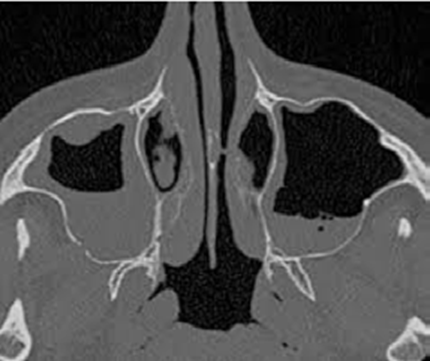

La tomodensitométrie abdominale avec opacification confirmait cette cholécystite avec un foie hétérogène, siège de multiples microlésions arrondies hypodenses, rehaussées légèrement après injection de produit de contraste (Figures 3, 4).